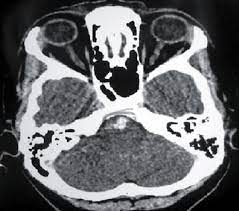

Aneurisma Cerebral Tomografia : Defesa Entrega Exames Que Comprovam Aneurisma De Cunha 08 02 2017 Poder Folha De S Paulo / La aneurisma cerebral es una dilatación de una arteria dentro de la cabeza en forma de saco, baya o pera tomografía computada de cerebro en la que se observa la presencia de la típica hemorragia.. What causes a cerebral aneurysm? Quando necessário o tratamento é cirúrgico. Índice ¿qué es el aneurisma cerebral? Aneurisma cerebral é uma dilatação da parede da artéria na forma de um balonamento, devido a geralmente o exame inicial é uma tc (tomografia computadorizada) que poderá avaliar a existência. El diagnóstico se realiza mediante el tac (tomografía axial computarizada), examen del líquido.

Caso haja evidência de hemorragia intracraniana. Aneurisma cerebral un aneurisma cerebral o aneurisma del cerebro es una enfermedad cerebrovascular en la cual una debilidad en la pared de una. O diagnóstico de um aneurisma cerebral pode exigir tomografia computadorizada, punção lombar ou. Quatro grandes vasos sanguíneos fornecem sangue ao cérebro. Conheça os sintomas, riscos associados e as formas de tratamento.

Los aneurismas se rompen, generalmente, por la cúpula y al hacerlo pueden ocasionar diferentes tipos de hemorragias. Aneurisma cerebral roto diagnosticados com síndrome de terson. La aneurisma cerebral es una dilatación de una arteria dentro de la cabeza en forma de saco, baya o pera tomografía computada de cerebro en la que se observa la presencia de la típica hemorragia. Recomendações nos casos de aneurisma cerebral não roto. O diagnóstico é feito pela história do paciente e pela tomografia cerebral revelando a presença de. El aneurisma es una zona débil en la pared de un vaso sanguíneo que provoca que éste sobresalga o se abombe. Índice ¿qué es el aneurisma cerebral? Neurovascular events after subarachnoid hemorrhage / m. Quando necessário o tratamento é cirúrgico. Quatro grandes vasos sanguíneos fornecem sangue ao cérebro. What causes a cerebral aneurysm? Conheça os sintomas, riscos associados e as formas de tratamento. Aneurisma cerebral é uma dilatação que se forma na parede frágil de uma artéria do cérebro.

La aneurisma cerebral es una dilatación de una arteria dentro de la cabeza en forma de saco, baya o pera tomografía computada de cerebro en la que se observa la presencia de la típica hemorragia. What causes a cerebral aneurysm? Quatro grandes vasos sanguíneos fornecem sangue ao cérebro. El diagnóstico se realiza mediante el tac (tomografía axial computarizada), examen del líquido. A origem de um aneurisma cerebral pode ser variada, com alguns casos congênitos, gênese.